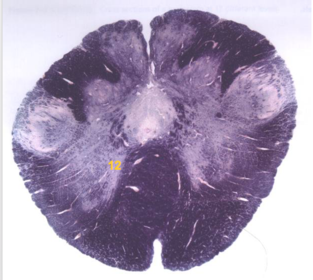

| Nucleus gracilis | |

| Accessory nucleus | |

| Medial longitudinal faciculus | |

| Pyramidal decussation | |

| Medullary pyramids | |

| Anterior spinocerebellar tract | |

| ALS | |

| Posterior spinocerebellar tract | |

| Spinal tract of V | |

| Spinal nucleus of V | |

| Nucleus cuneatus | |

| Fasciculus cuneatus | |

| Fasciculus gracilis | |

| Central canal | |